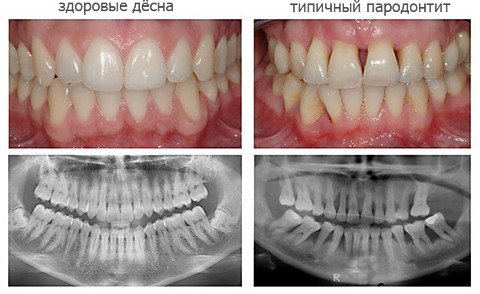

Фото

Пародонтит — воспалительное заболевание, поражающее ткани, поддерживающие зубы, что может привести к их утрате. Многие не осознают серьезность проблемы, которая вызывает дискомфорт в деснах и негативно влияет на общее здоровье. Основные факторы, способствующие развитию пародонтита: недостаточная гигиена полости рта, курение, наследственность и системные заболевания, такие как диабет.